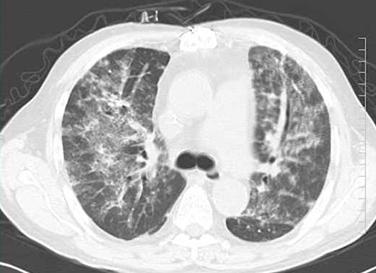

CT所見としてはすりガラス影、網状影の広がりが確認されます。間質性肺炎疑いです。